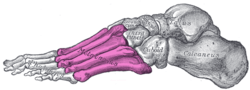

![]() Skeleton of foot. Superior view. Metatarsals shown in green. | |

![]() Skeleton of left foot. Lateral aspect. Metatarsals shown in purple. | |